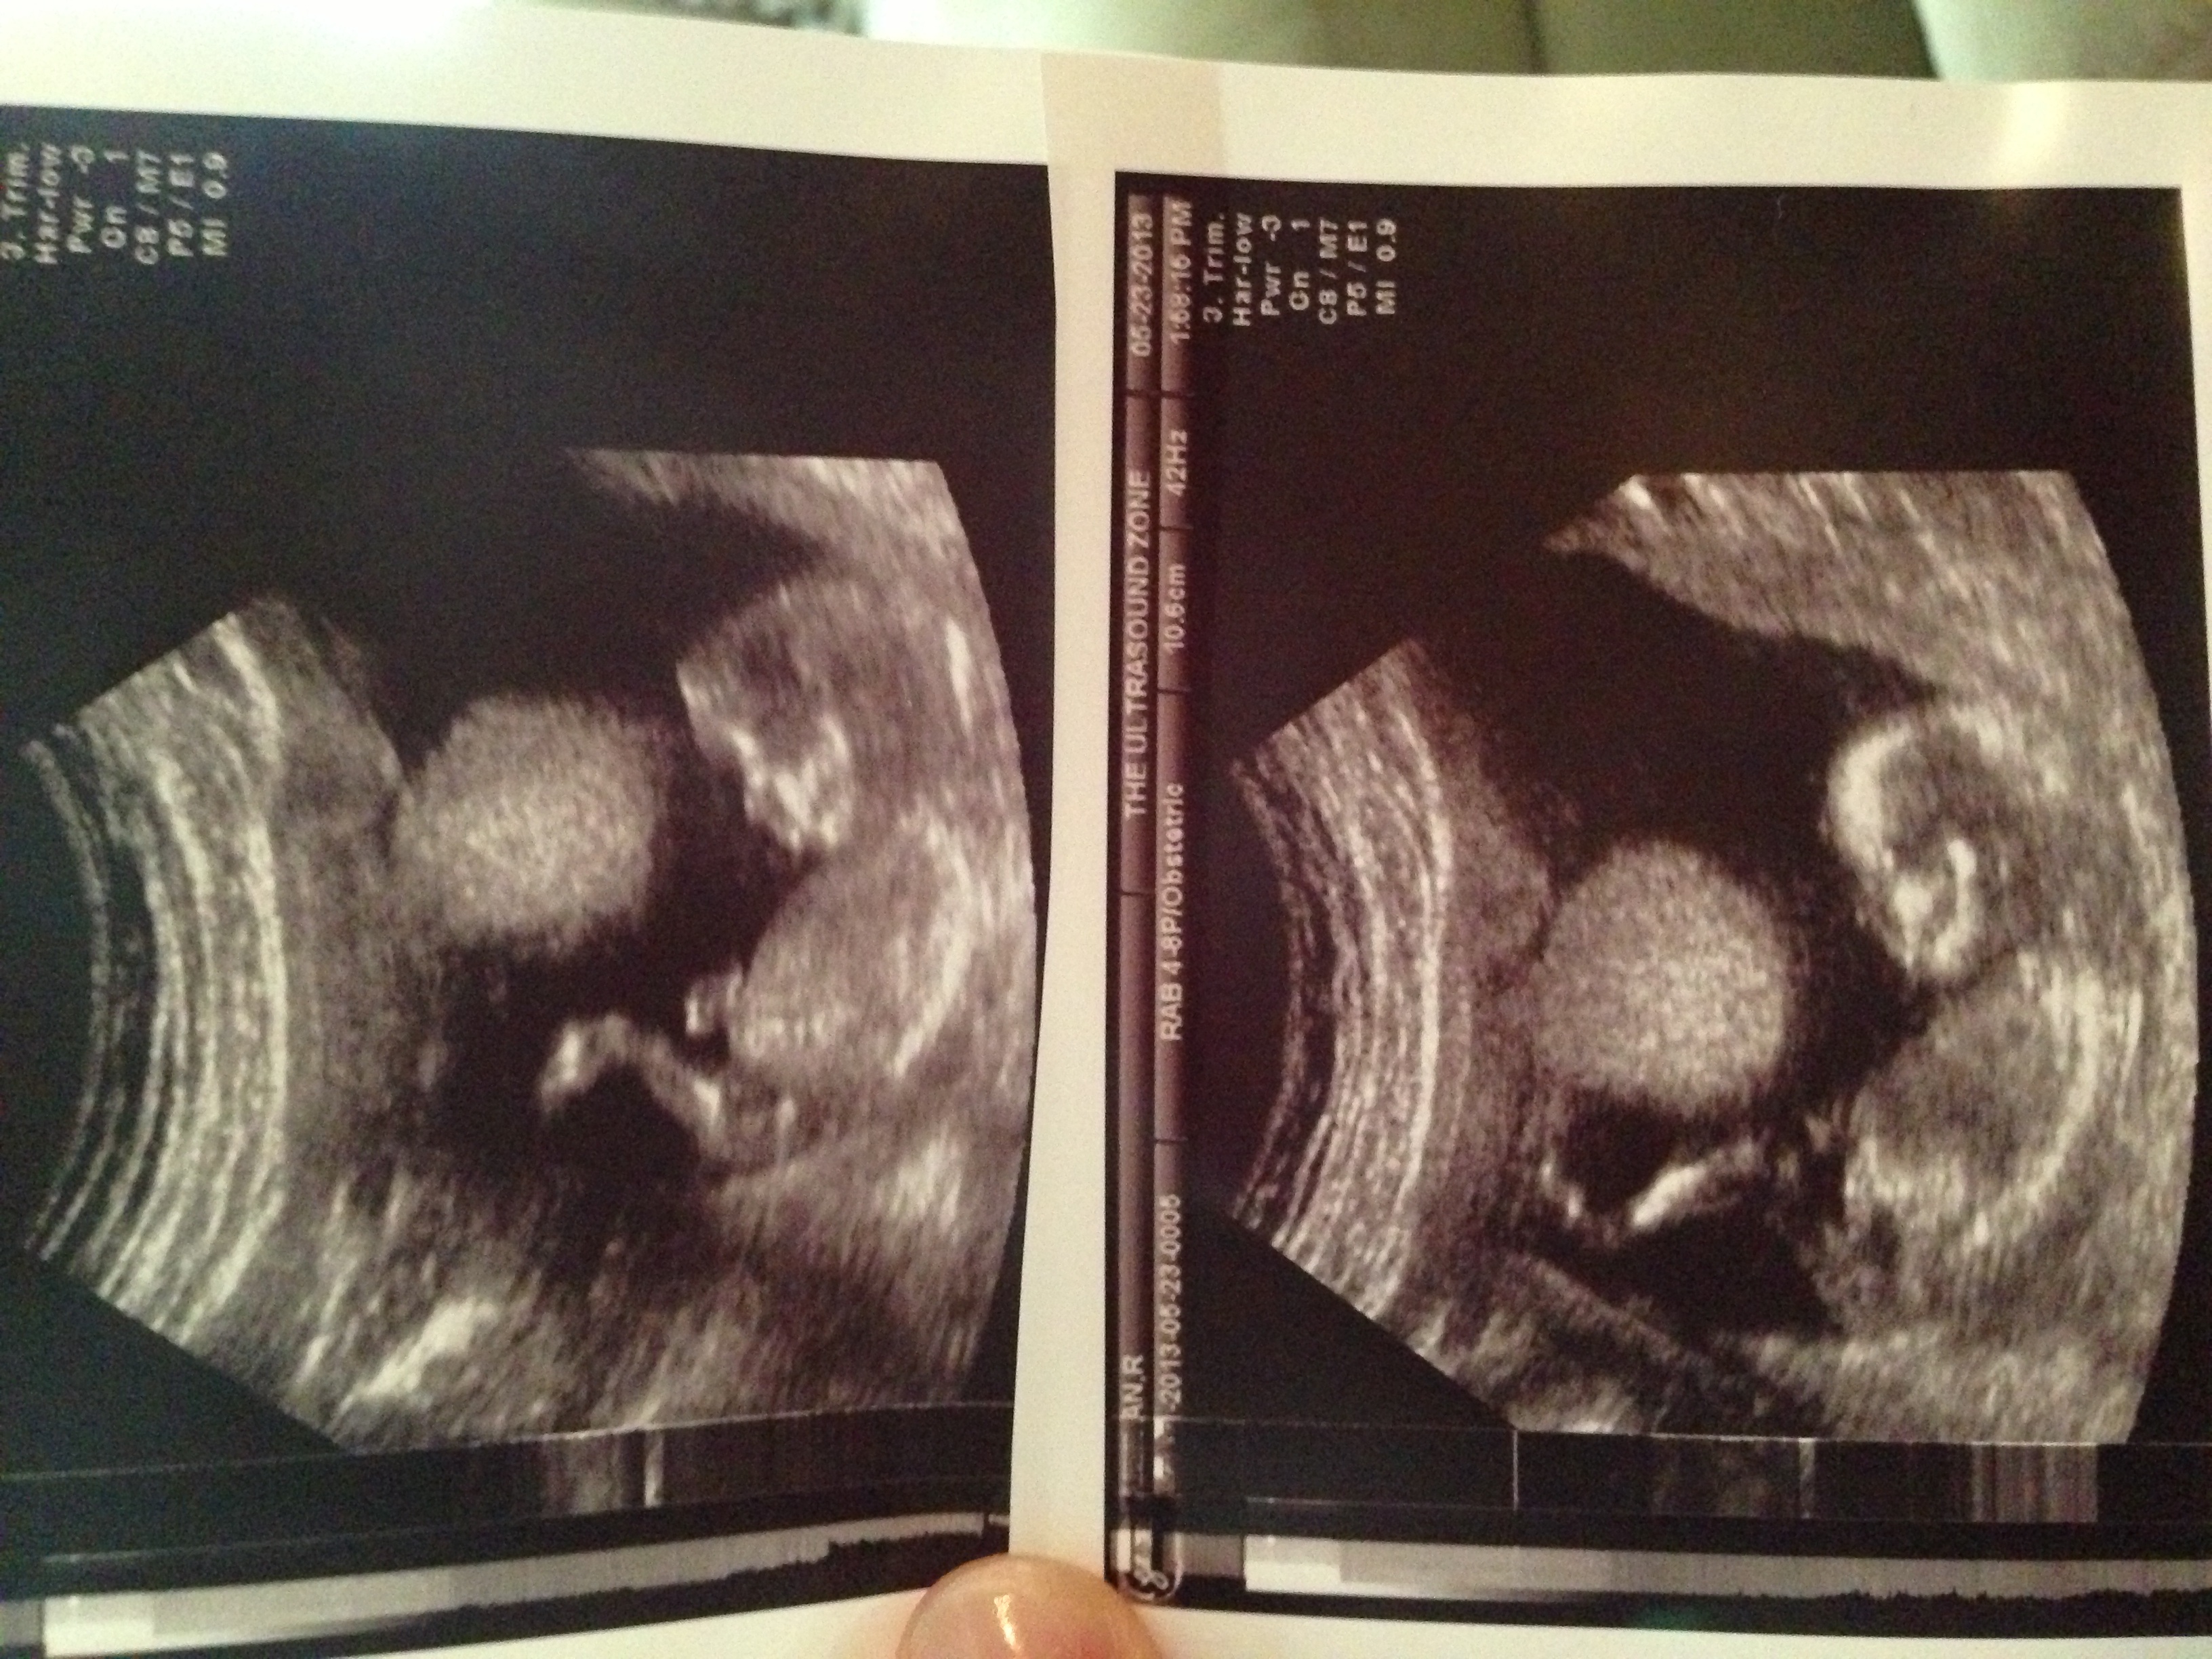

13 weeks 2 day U/S

Attachment 11549The tech was leaning toward girl but wasn't positive and something is telling me boy. What do you think? Thanks for the guesses!

the little bulb at the end makes me lean more towards boy, but thats just a guess

I thought girl, I thought it would be more angled by this time. just a guess GL.

The angle makes me think girl too but the nub looks more boy. im 50/50 on this one xxx

Very girly for this gestation.

Slight boy lean

Having seen the gestation for when this pic was taken I'd guess more girl. Still confused by bulb at end though...